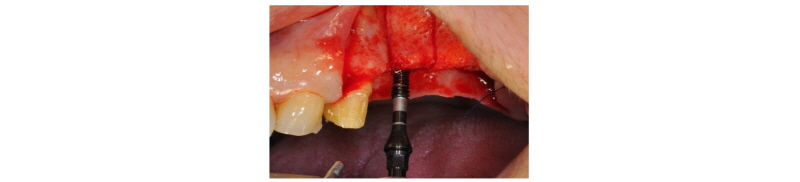

57세의 여성 환자로 기존 브릿지 보철 수복물(#24-27)의 상악 좌측 제 2대구치의 심한 우식으로 인해 내원하여 해당 치아를 발거하였다(Fig. 1). 상악 좌측 제 1 소구치는 근관치료를 시행한 후 보철 수복하기로 하였고 기존 pontic 부위였던 좌측 제 2 소구치와 발거된 제 2 대구치 부위에 #25i, #27i 2개의 임플란트 식립을 통한 브릿지 보철 수복물을 계획하였다(Fig. 2). 기존 pontic으로 유지되었던 좌측 제 2 소구치 부위는 치조제의 심한 수평적 치조골 흡수를 구강 내 임상검사를 통해 확인할 수 있었다. 전층 판막 형성후 상악 좌측 제 2 소구치 부위의 치조정 폭경은 약 2 mm 정도로 측정되었다(Fig. 3, 4). 치조골의 구개측에 약 1 mm의 치조골이 남도록 high speed carbide round bur를 이용하여 치조정에 horizontal intraosseous groove를 형성하였고 협측골의 근심, 원심측에 2개의 vertical intraosseous groove를 형성하였다(Fig. 5). Chisel과 ridge spreader drill (RS kit, Dentium, Korea)을 이용하여 점차적으로 협측 골판을 구개측으로부터 분리시켰다(Fig. 6). Osteotome을 이용, 식립 깊이까지 적용하여 임플란트 식립 부위를 형성하였고 Ø4.3 × 10 mm (Implantium, Dentium, Korea) 임플란트를 식립하였다(Fig. 7). 발치 후 치유된 상악 좌측 제 2 대구치 부위는 상악동 거상술(수직 접근법)을 시행, 골이식을 한 후 4.8 × 10 mm (Implantium, Dentium, Korea)를 식립하였다(Fig. 8). 이후 이종골 이식재(Bio-Oss®, Geistlich, Switzerland)를 식립된 임플란트와 협,구개 측 치조골판 사이의 gap과 협측골판 상방에 적용하고 흡수성 교원질 차폐막(Bio-Gide®, Geistlich, Switzerland)로 피개한 다음 감장절개를 통해 장력없이 봉합하였다(Fig. 9-11). 이후 구강 내 검사 및 방사선 검사를 통해 수술부위 치유상태를 확인하였고 특이한 임상적 소견없이 정상적으로 잘 치유되었다(Fig. 12). 약 3개월 10일 정도의 치유기간 후 이차수술을 시행하였다(Fig. 13). 판막 거상 후 치조제 분할술을 시행하였던 상악 좌측 제 2 소구치 부위에 잘 형성된 신생 골양조직이 관찰되었다(Fig. 14). 상악 좌측 제 2 소구치 부위와 상악 좌측 제 2 구치 부위에 치유지대주를 장착하였고 상악 좌측 제 1 대구치 부위에 추가적으로 임플란트를 1회법으로 식립하였다(Fig. 15). 이차수술 이후 정상적으로 치유가 진행되어 약 2개월 후 최종 보철물 수복을 하였다(Fig. 16, 17). 약 1년 정도의 follow-up시 구강 내 검사와 방사선 검사를 통해서 임플란트 주위 연조직과 변연골이 잘 유지되고 있음을 확인하였다(Fig. 18).

Fig. 11. Flap was closed with tension-free sutures. |